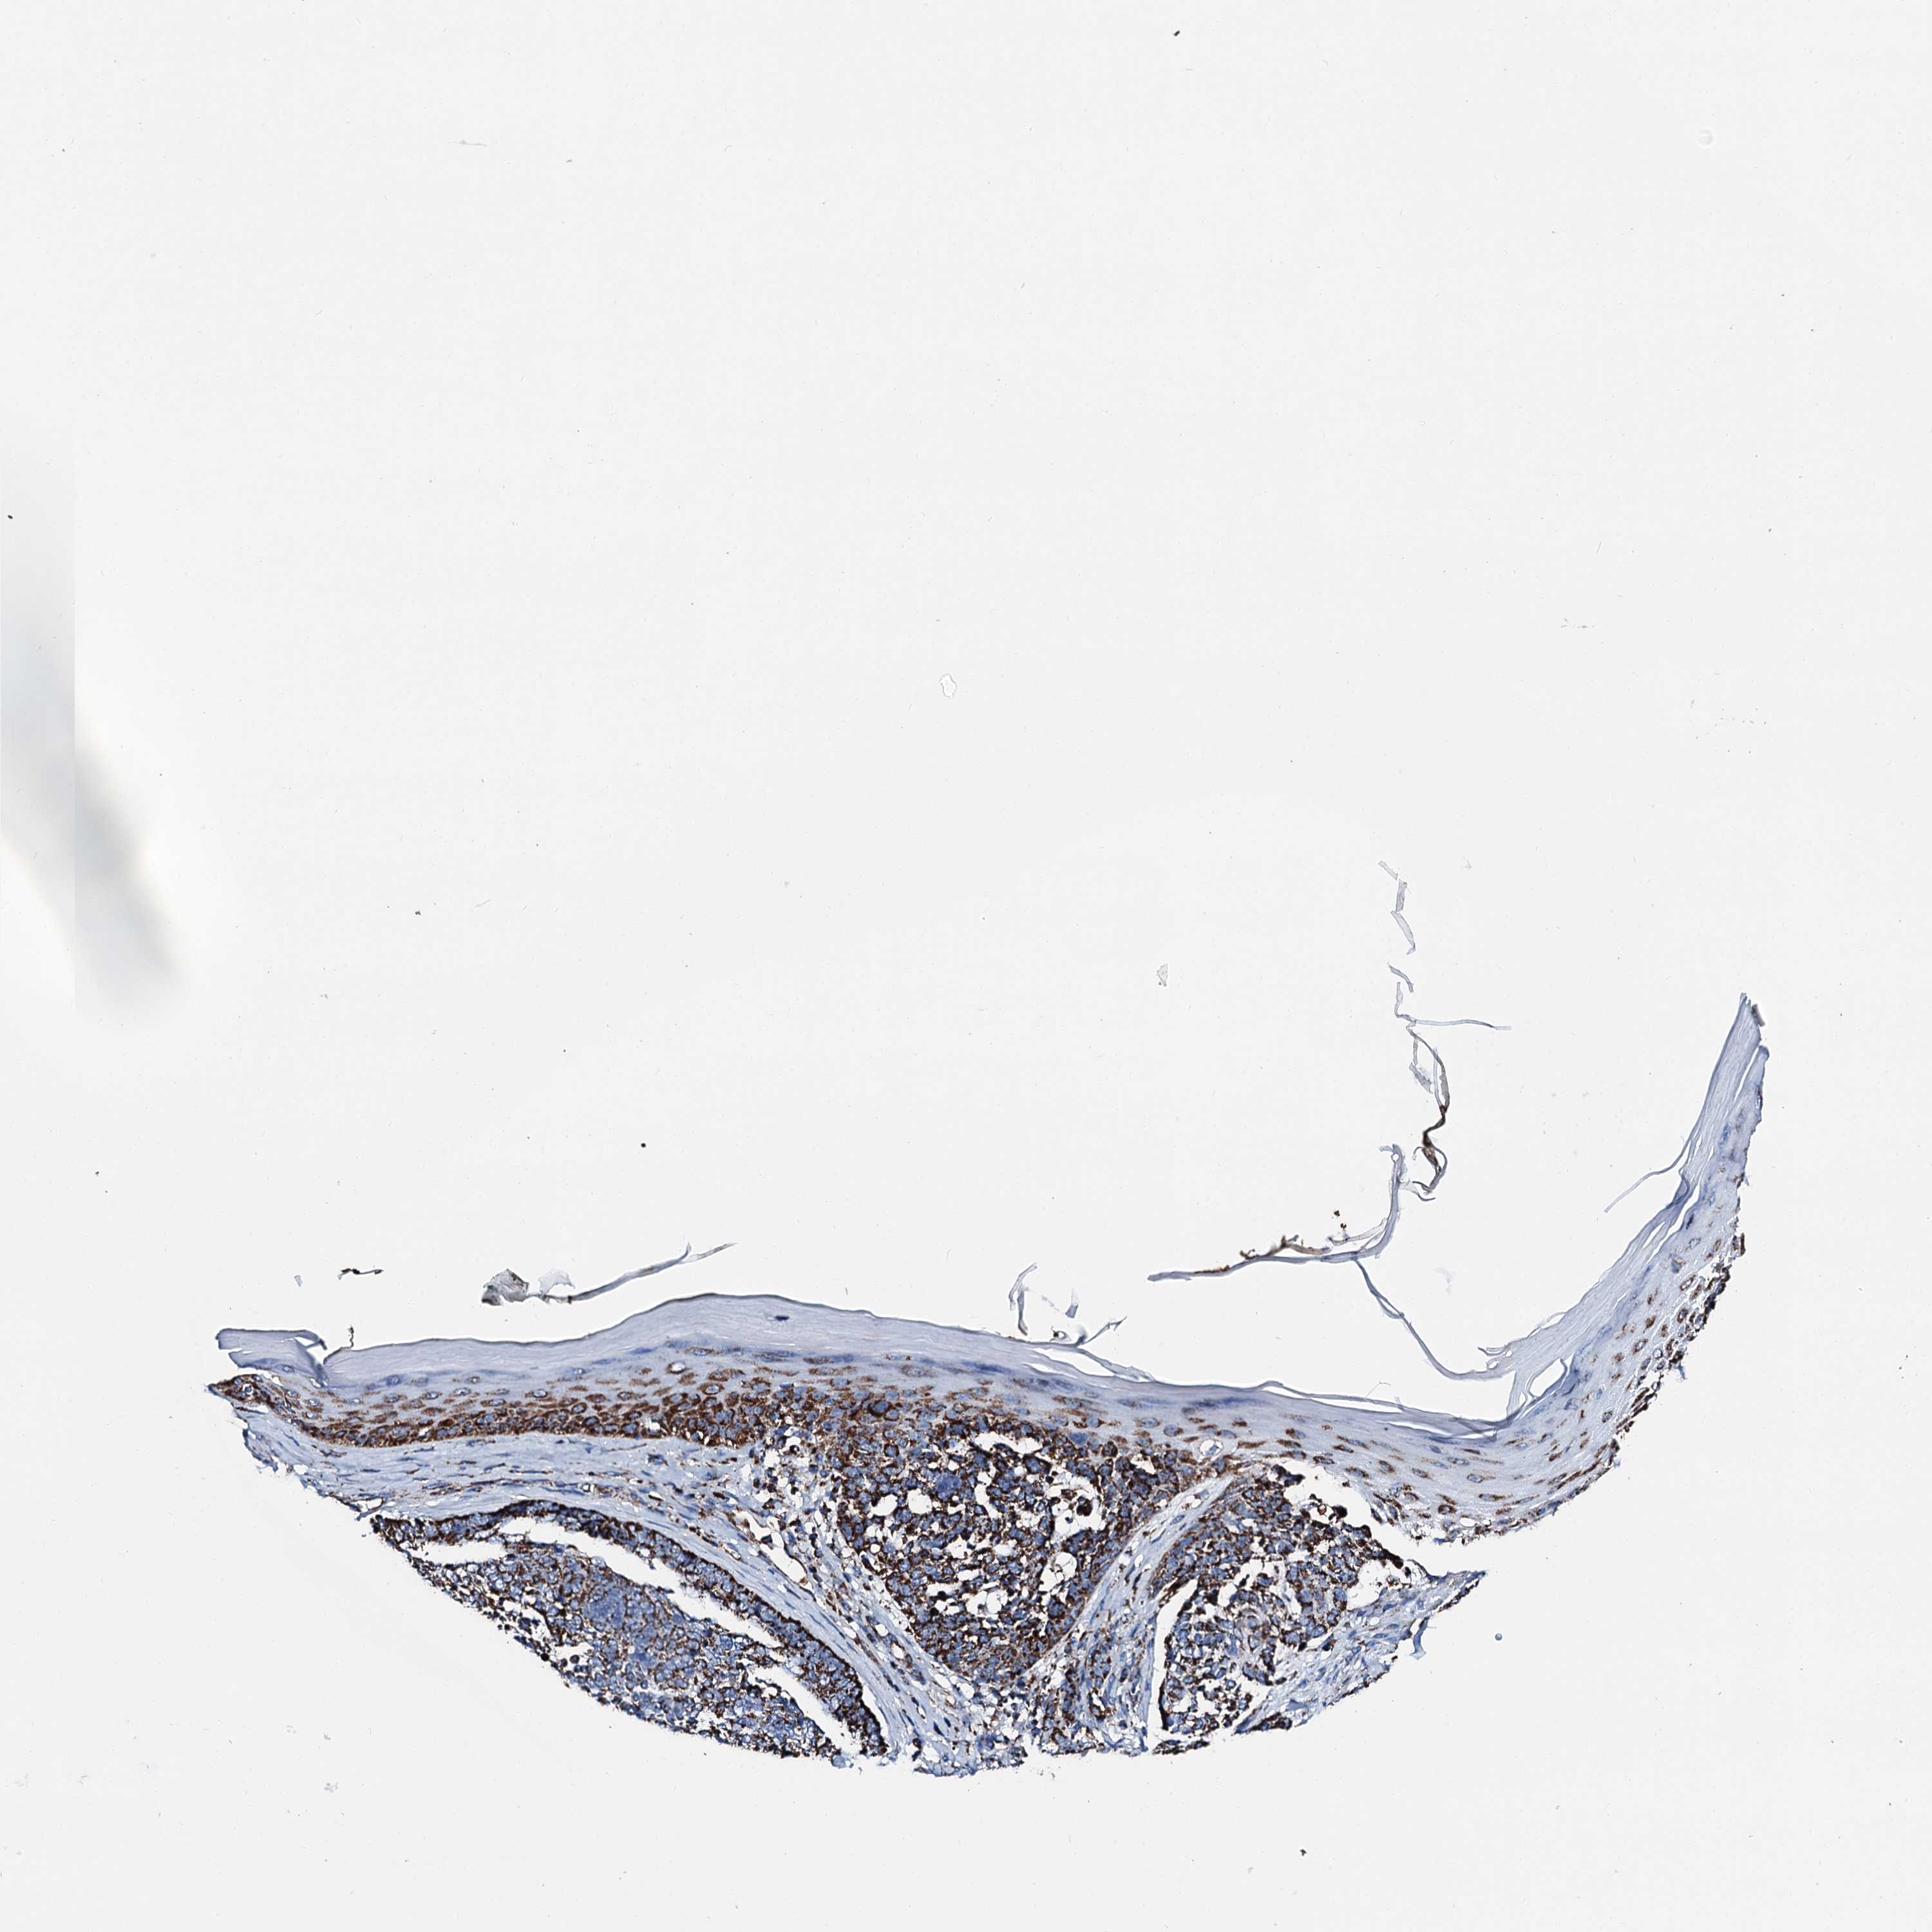

SKIN CANCER - Protein expressioni

A mouse-over function shows sample information and annotation data. Click on an image to view it in a full screen mode. Samples can be filtered based on level of antibody staining by selecting one or several of the following categories: high, medium, low and not detected. The assay and annotation is described here.

Antibody staining in the annotated cell types in the current human tissue is reported as not detected, low, medium, or high, based on conventional immunohistochemistry profiling in selected tissues. This score is based on the combination of the staining intensity and fraction of stained cells.

Each image is clickable and will lead to virtual microscopy that enables deeper exploration of all samples and also displays staining intensity scores, fraction scores and subcellular localization as well as patient and tissue information for each sample.

Antibody HPA043888

Staining

High

Medium

Low

Not detected

Intensity

Strong

Moderate

Weak

Negative

Quantity

>75%

75%-25%

<25%

None

Location

Nuclear

Cytoplasmic/membranous

Cytoplasmic/membranous,nuclear

Basal cell carcinoma

Squamous cell carcinoma, NOS

Squamous cell carcinoma, metastatic, NOS